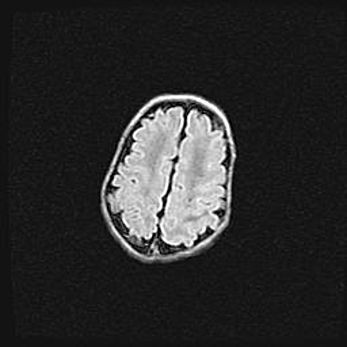

Церебральная ишемия II.

Возраст: 5 дней

Вес: 3400 г

Пол: женский

Окружность головы: 35 см

Срок гестации: 39 недель

Церебральная ишемия – это заболевание, характеризующееся недостаточностью (гипоксией) либо полным прекращением (аноксией) снабжения мозга кислородом по причине закупорки одного или нескольких сосудов. Это приводит к  что метаболическим расстройствам различной степени тяжести в тканях головного мозга, развитию коагуляционных некрозов и гибели нейронов.